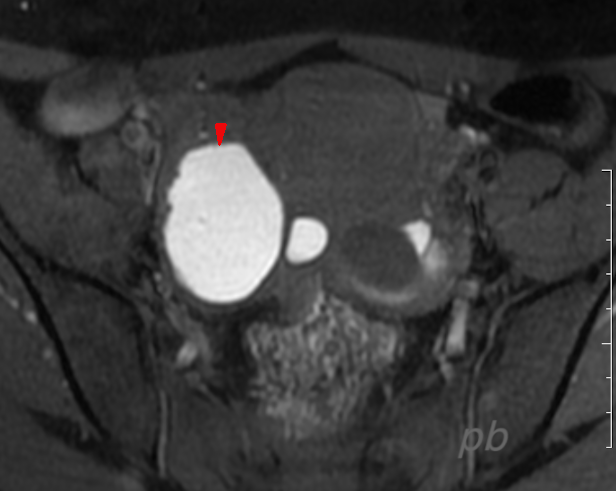

IRM axial T2

10 mois plus tard, récidive du kyste droit.

Volumineux kyste à droite, contenant des végétations internes (►) et externes (►).

Les zones tissulaires s’étendent sur le péritoine (★). On en retrouve en particulier en sus-vésical et dans le Douglas (non montrées).

Ascite (★).

Adénopathie iliaque gauche (★)

Prise de contraste après injection de gado.

Conclusion : Tumeur ovarienne maligne et carcinomatose péritonéale.